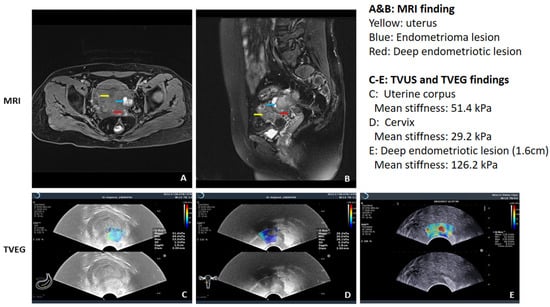

- Ding, D.; Chen, Y.; Liu, X.; Jiang, Z.; Cai, X.; Guo, S.W. Diagnosing Deep Endometriosis Using Transvaginal Elastosonography. Reprod. Sci. 2020, 27, 1411–1422. [Google Scholar] [CrossRef]

- Liu, X.; Ding, D.; Ren, Y.; Guo, S.W. Transvaginal Elastosonography as an Imaging Technique for Diagnosing Adenomyosis. Reprod. Sci. 2018, 25, 498–514. [Google Scholar] [CrossRef]